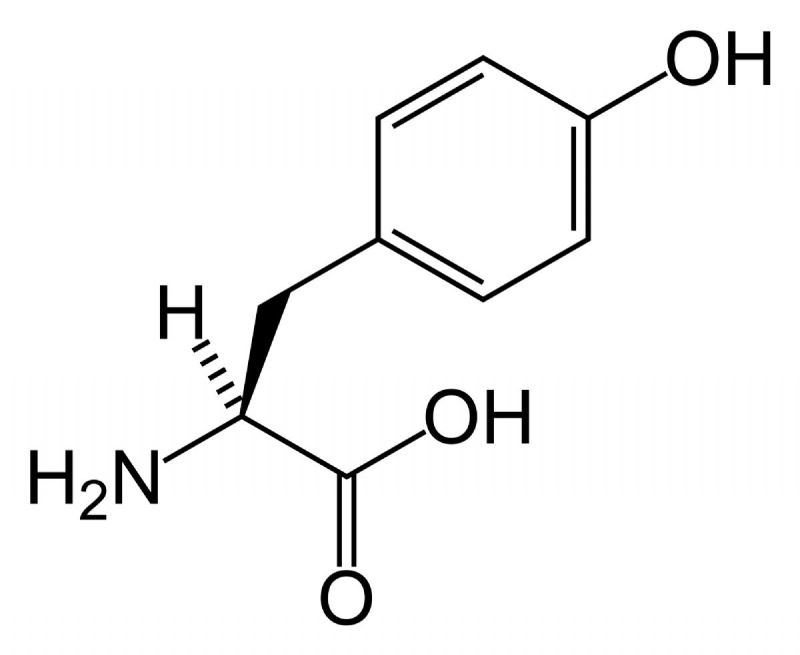

fenilalanin- tirozin amino asitleri: aminoasitler arasında özellikle tirozine karşı bi hayranlığım var. neredeyse her taşın altından(abartıyorum) çıkan bir aminoasit. öncelikle fenilalanin ve tirozinin moleküler yapısından bahsetmem gerekir. bu iki aminoasit halkasal bir radikal gruba sahiptir. bu grup benzen halkasının türevleri olan fenil ve fenol gruplarını taşır. ve hormonlar nörotransmitterler ve sitokinler arasında benzen fenol ve fenil halkası bulunduran tüm yapılar tirozin ve fenilalanin aminoasitlerinden sentez edilir.

bunları fotoğraf ile göstereyim:

şu gördüğünüz tirozin, üstteki halkasal yapıya dikkatli bakın

evet... bu hormonların hepsi tiroksin aminoasitinden sentezlenir. çünkü tiroksin aminoasitinden bu halkasal yapı alınarak başka moleküller ile birleştirilip bu hormonlar oluşturulur. bu halkasal yapılar, benzen, fenil- fenol ve benzeri yapılar şeker, yağ gibi besinlerde bulunmaz. yalnız tirozin ve fenilalanin aminoasitinden elde edilebilir. dışarıdan almak zorundasınız, zira vücudumuzun bu molekülleri sentezleme yetenekleri yoktur-sınırlıdır. ve bu aminoasitler olmadan bu adı geçen hormonları sentezleyemezsiniz. bu da vücudunuzun genel işleyişini bozarak ciddi metabolik hastalıklara yol açacaktır.